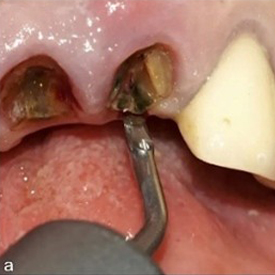

Şekil 2: Piezoelektrik periotom (W&H EX1) kullanılarak yapılan sindesmotomi (a), damak parçaları seviyesinde periodontal ligament boşluğuna yerleştirilmiştir (b).